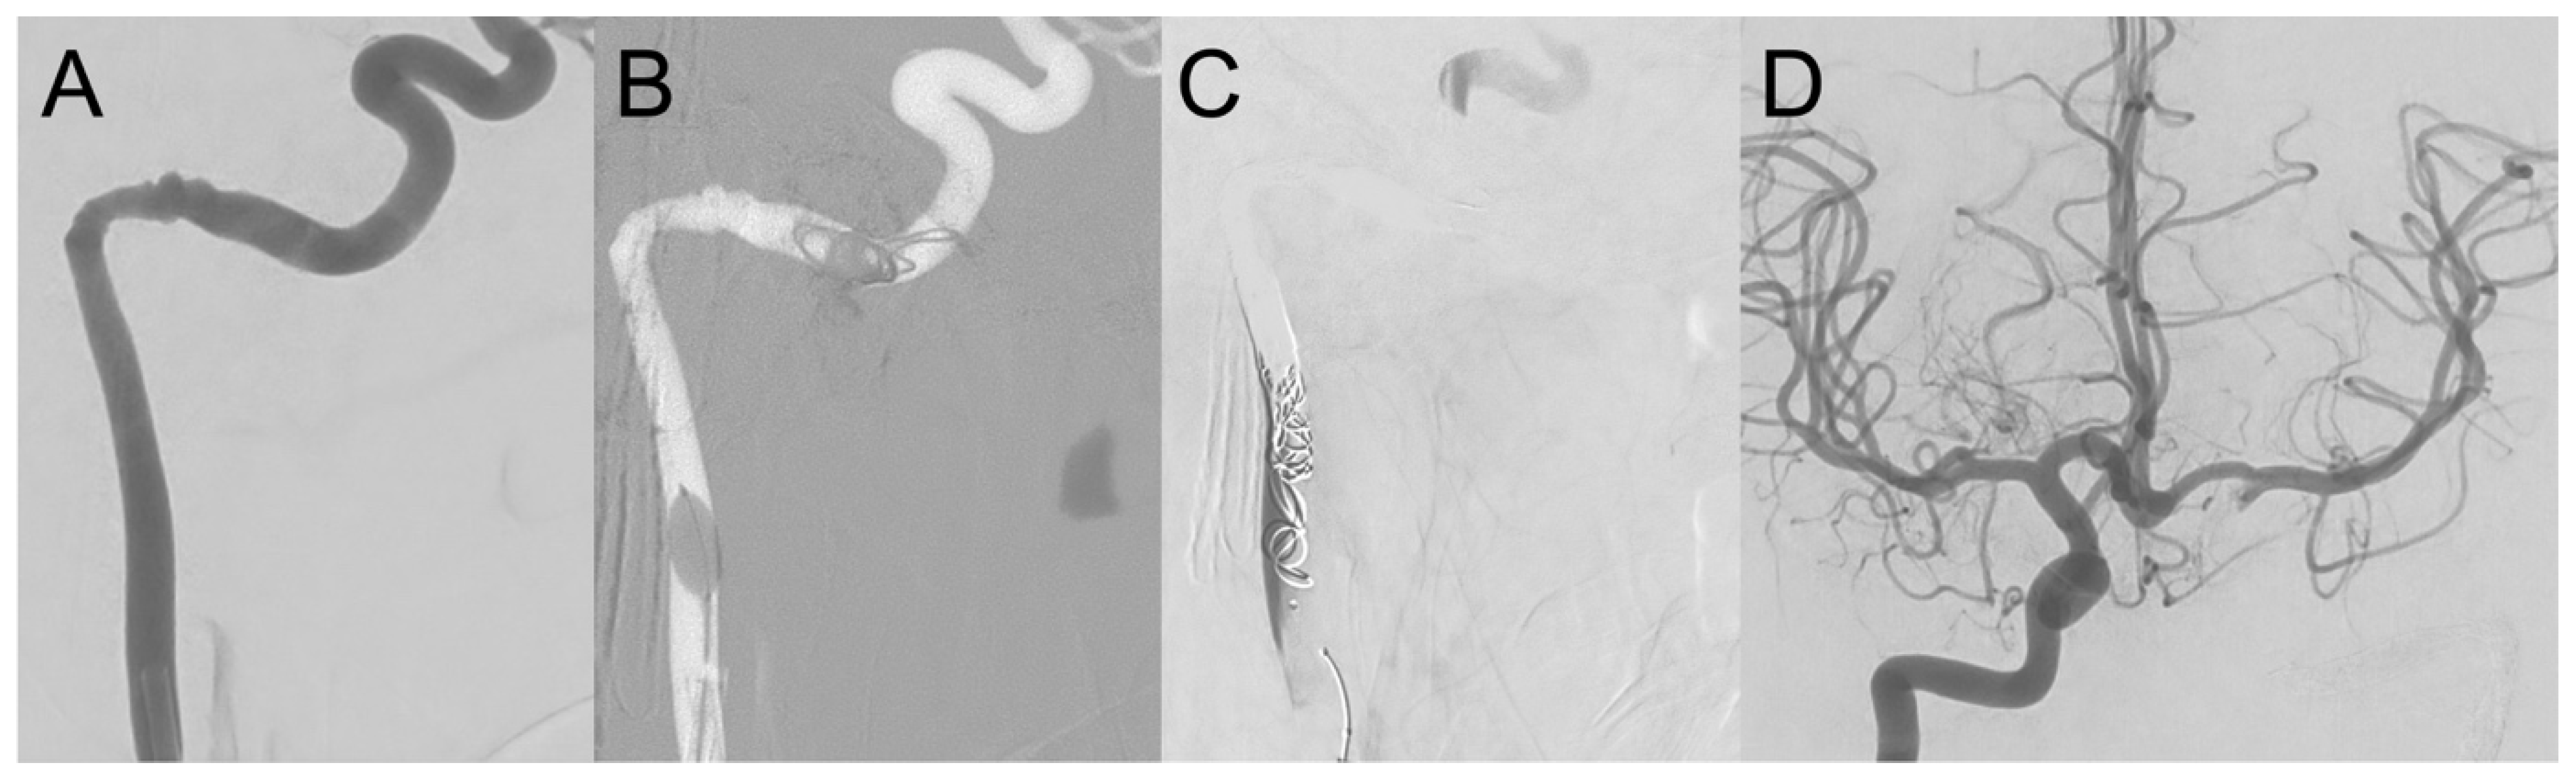

Figure 3. (A) Digital subtraction angiography (DSA) of the left ICA of case 2 in a lateral projection showing pseudoaneurysms at the proximal petrous (tympanic) section. (B) Coil embolization with bare metal coils was performed from the distal petrous to the distal cervical ICA under proximal flow arrest using a highly compliant dual lumen balloon, since flow-related coil migration to the distal ICA must be avoided at all costs. (C) DSA of the left ICA post-embolization in the same projection showing contrast medium stasis proximally, and partial collateralization of the cavernous ICA via external carotid artery branches. (D) Substantial collateralization from the right ICA to the left middle cerebral artery via anterior communicating artery is illustrated by DSA with injection from the right ICA.

During myringotomy, profuse arterial bleeding occurred from the left middle ear. Manual compression and EAC packing achieved initial hemostasis. Subsequent CT angiography identified an aICA running through the left middle ear as the source of bleeding (Figure 1C,D). Because of the high risk of re-bleeding and the presence of a large anterior communicating artery segment suggestive of good collateral circulation, a balloon test occlusion was not performed. Immediate coil embolization of the left ICA from the distal petrous to the distal cervical section was conducted via a right femoral access (Figure 3). A highly compliant dual lumen balloon (Scepter CS 4 × 11 mm, Terumo Neuro) was used to achieve flow arrest and to avoid coil migration during the procedure [23]. Post-procedure, he remained stable, with no post-procedural focal neurological deficit after extubation on the same day. On the third postoperative day, the ear packing was removed without complications.